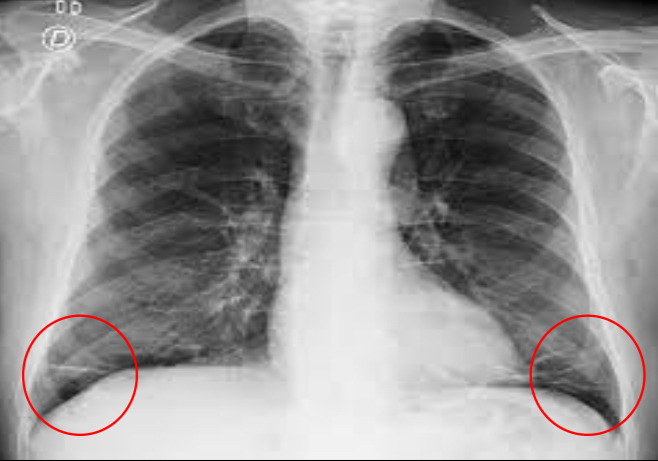

que patrón pulmonar es

A

consolidación

en este patrón no podemos ver estructuras, se verá blanco muy sólido, veremos una radiopacidad en RX o una hiperdensidad en TC de forma irregular y difusa